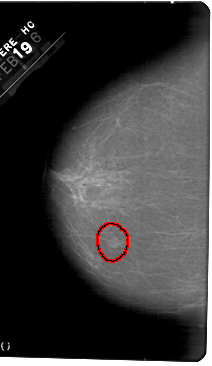

A_1346_1.RIGHT_MLO

RIGHT_CC LINES 5491 PIXELS_PER_LINE 3316 BITS_PER_PIXEL 12 RESOLUTION 43.5 NON_OVERLAY

FILE: A_1346_1.LEFT_CC.OVERLAY

TOTAL_ABNORMALITIES 1

ABNORMALITY 1

LESION_TYPE MASS SHAPE OVAL MARGINS ILL_DEFINED

ASSESSMENT 4

SUBTLETY 4

PATHOLOGY BENIGN

TOTAL_OUTLINES 1

BOUNDARY